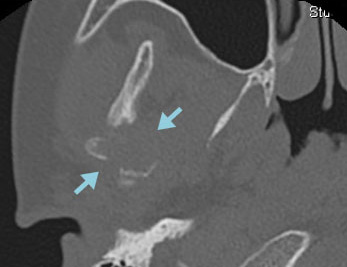

症例:7歳

右下顎骨にLCHの骨再発をきたした。HU内服治療を開始後、溶骨部分の順調な修復が認められた。

CT 骨条件

ハイドロキシウレア開始時  2か月後

2か月後  4か月後